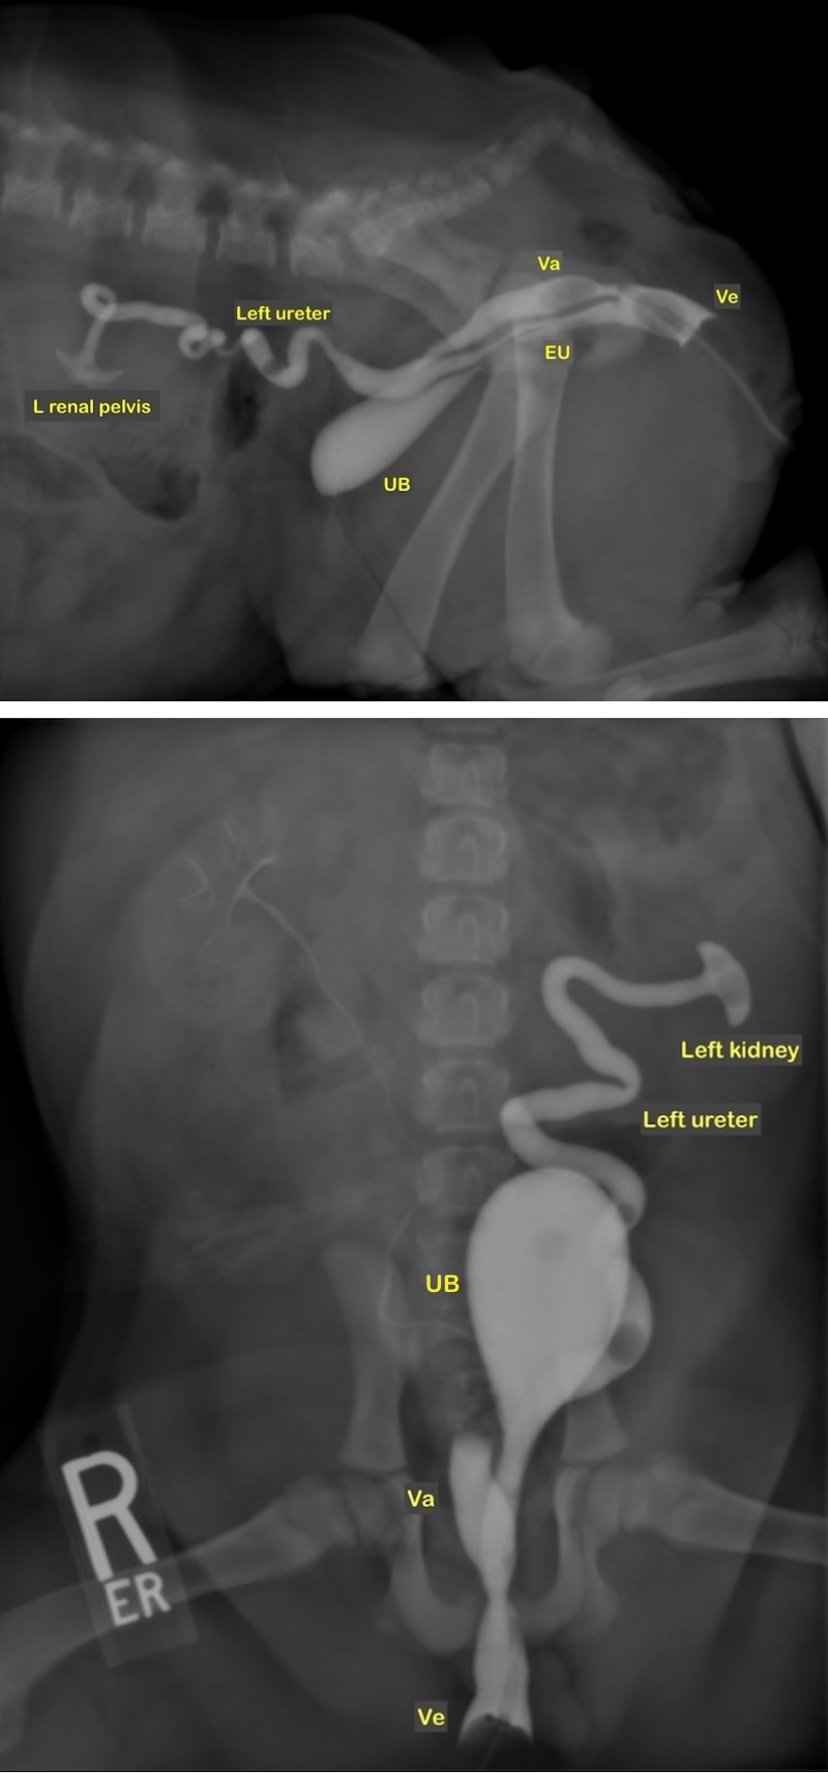

-Right lateral radiography in a female dog affected by ectopic ureter ...

-Ventrodorsal radiography in a dog affected by an ectopic ureter ...